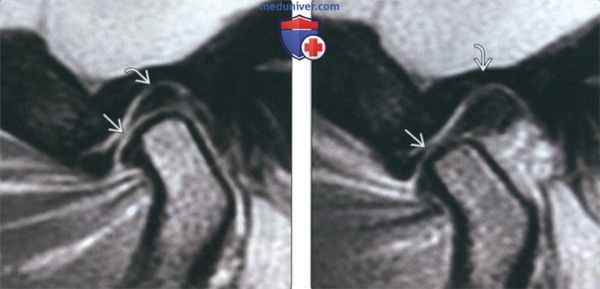

(Слева) На косой сагиттальной МРТ (Т2 ВИ) левого ВНЧС с закрытым ртом визуализируются задний пучок и переходная зона диска, нормально расположенные относительно мыщелка.

(Справа) На косой сагиттальной МРТ (Т2 ВИ) с открытым ртом у этого же пациента определяется ограничение трансляции мыщелка. Отсутствует трансляция диска по заднему скату суставною возвышения. Задний пучок диска занимает наиболее высокое положение в суставной ямке. Область соединения переходной зоны и переднею пучка находится между мыщелком и суставным возвышением.